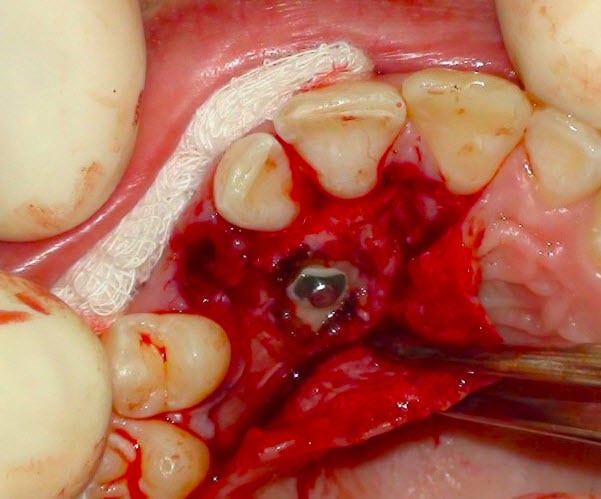

Regarde une nouvelle fois la photo per-op.

Tu penses vraiment que je pouvais passer par le nez pour coller quelque chose en vestibulaire ?